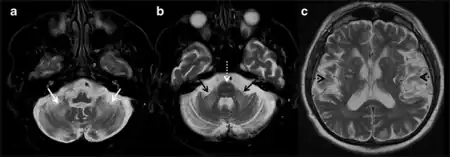

Clinical findings are divided into major and minor symptoms. Major symptoms include intention tremor and gait ataxia. Minor symptoms such as parkinsonism, short-term memory deficit, and executive function decline can further contribute to a diagnosis of FXTAS. Radiological findings are similarly divided into major and minor categories. As patients with FXTAS can have distinct brain scans from other movement disorders, a scan showing white matter lesions of the middle cerebellar peduncle is a major finding that can be attributed to FXTAS. Overall or generalized brain tissue atrophy and cerebral white matter lesions can also be minor indicators for a diagnosis.[12]